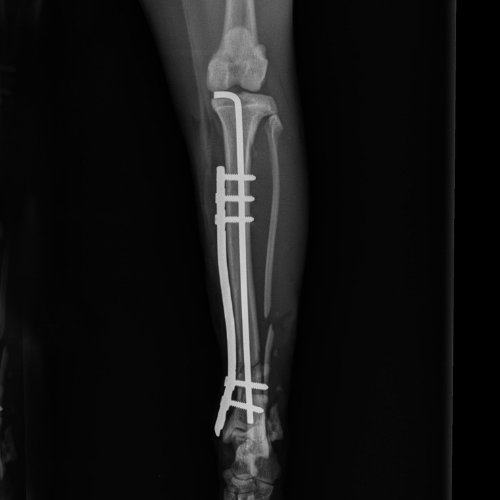

El servicio de traumatología está dirigido por Enrique Senís, especialista en traumatología y ortopedia por la Universidad Complutense de Madrid . Estamos orientados al diagnóstico y tratamiento de patologías del sistema musculoesquelético, incluyendo fracturas, luxaciones, rotura de ligamento cruzado y demás alteraciones articulares y deformidades óseas.

Disponemos de medios diagnósticos avanzados y aplicamos técnicas quirúrgicas de última generación en osteosíntesis, estabilización articular y corrección de deformidades, con el objetivo de restaurar la funcionalidad y minimizar el dolor en nuestros pacientes.